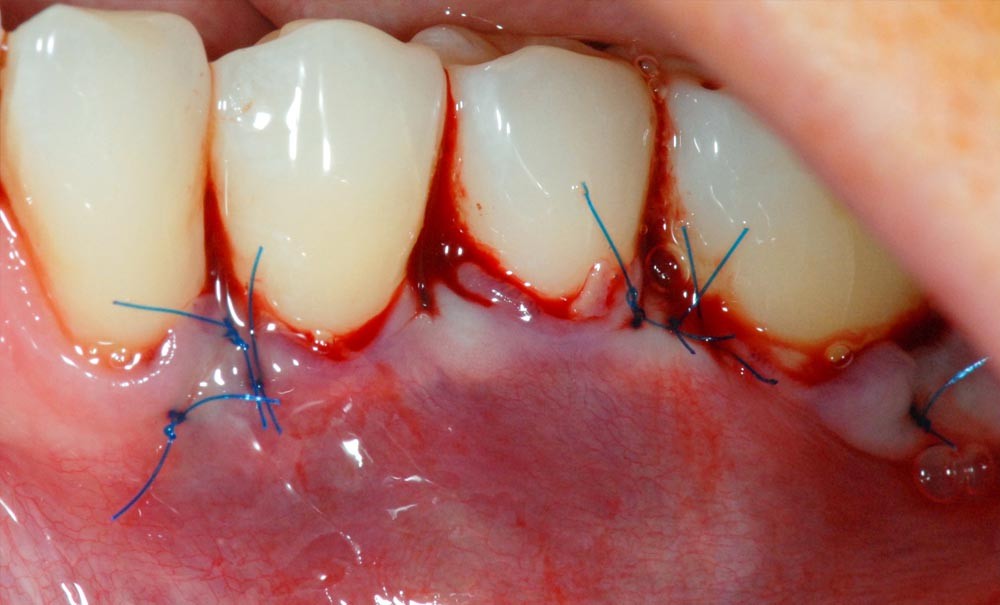

Cette technique permet de recouvrir des récessions gingivales contiguës par une traction coronaire après une dissection partielle superficielle au-delà de la ligne muco-gingivale. Grâce à un jeu d’incisions des papilles, les incisions de décharge ne sont pas nécessaires. Un greffon conjonctif prélevé au palais selon la technique de l’enveloppe [3] est placé sur les récessions et suturé en même temps que le lambeau par des points suspendus [4].

Dans notre cas clinique, l’intervention a duré un peu moins d’une heure.